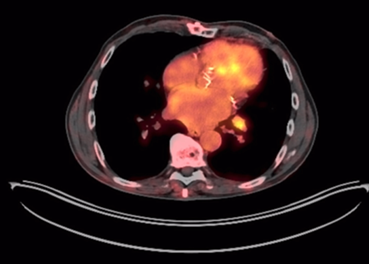

We present the case of a 69-year-old man with a history of hypertension and stage III chronic kidney disease, who in 2017 underwent left radical nephrectomy for clear cell renal carcinoma (pT1bN1M0, Fuhrman histological grade III). During oncological follow-up, the patient remained asymptomatic, with a normal physical examination. A positron emission tomography (PET-CT) scan incidentally revealed a hypometabolic thyroid nodule (SUVmax [2,6]), prompting the recommendation for monitoring. Subsequently, in 2022, asymptomatic primary hypothyroidism was diagnosed without palpable findings, and treatment with levothyroxine 50 mcg/day was initiated. Two years later, a cervical ultrasound revealed a 3.5 x 2.5 x 3 cm hypoechoic solid nodule with irregular margins, cystic components, and mixed vascularization, located in the lower pole of the left lobe, classified as TIRADS 4C (Figure 1), which was palpable. A fine-needle aspiration biopsy (FNAB) of the nodule was performed and yielded a Bethesda category III.

Figure 1

Cervical ultrasound. Heterogeneous thyroid nodule measuring 3.5 x 2.5 x 3 cm.

Source: SOLCA Intranet - Guayaquil.